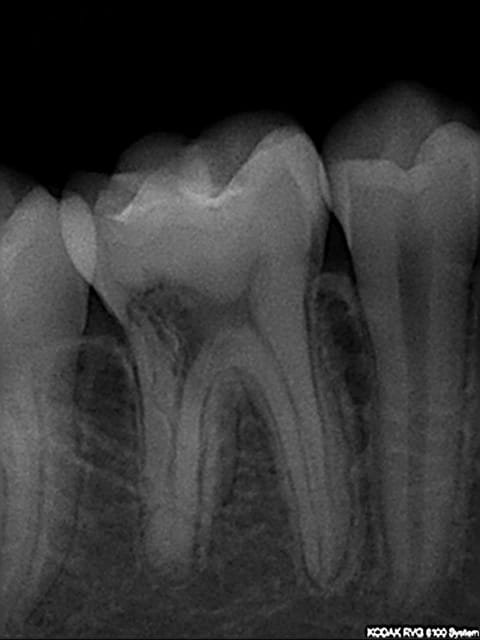

Patient de 14 ans

découverte sur pano d'une image radioclaire au niveau caméral de 46.

aucun signe clinique

vitalité positive

sondage paro ok

Pour moi il s'agit plutôt d'une résorption externe.

Il y a des chances que ce soit une séquelle d'un traitement ortho, mais parfois l'étiologie reste inconnue.

PS : si tu te lances dans l'endo...tu as une radix entomolaris (ou paramolaris)...ne l'oublies pas.